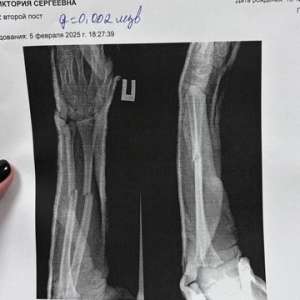

В Нижнекамске школьник просто так сломал девочке руки. Отец напавшего требовал родителей замять дело

Шестиклассник подошёл к однокласснице и спросил: "Тебя когда-нибудь бросали через прогиб?". Решив, что у мальчика очередная фаза, девочка попыталась отойти от него, но он схватил её и швырнул об пол.

Как итог: школьница находится в больнице с переломом обеих рук, ей предстоит длительная реабилитация. Но на этом история не закончилась, так как уже вскоре отец мальчика, узбек Абдурахмон Эшонов, пробрался в палату девочки и принялся убеждать её, что его сын сделал это случайно.